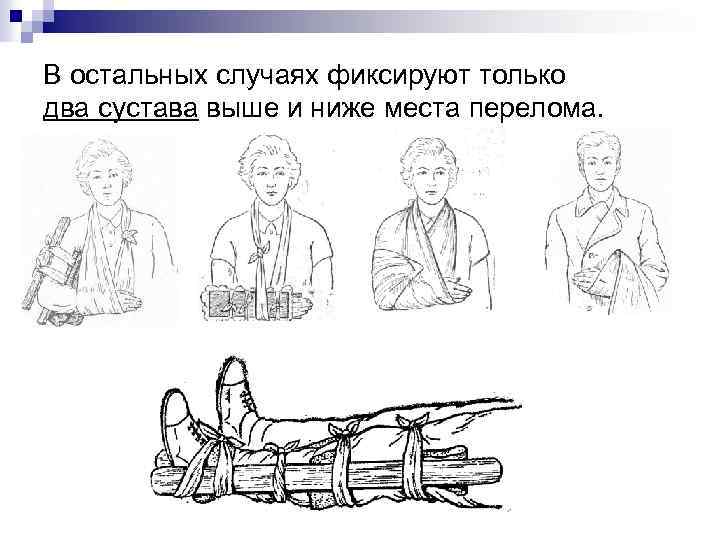

В остальных случаях фиксируют только два сустава выше и ниже места перелома.

В остальных случаях фиксируют только два сустава выше и ниже места перелома.